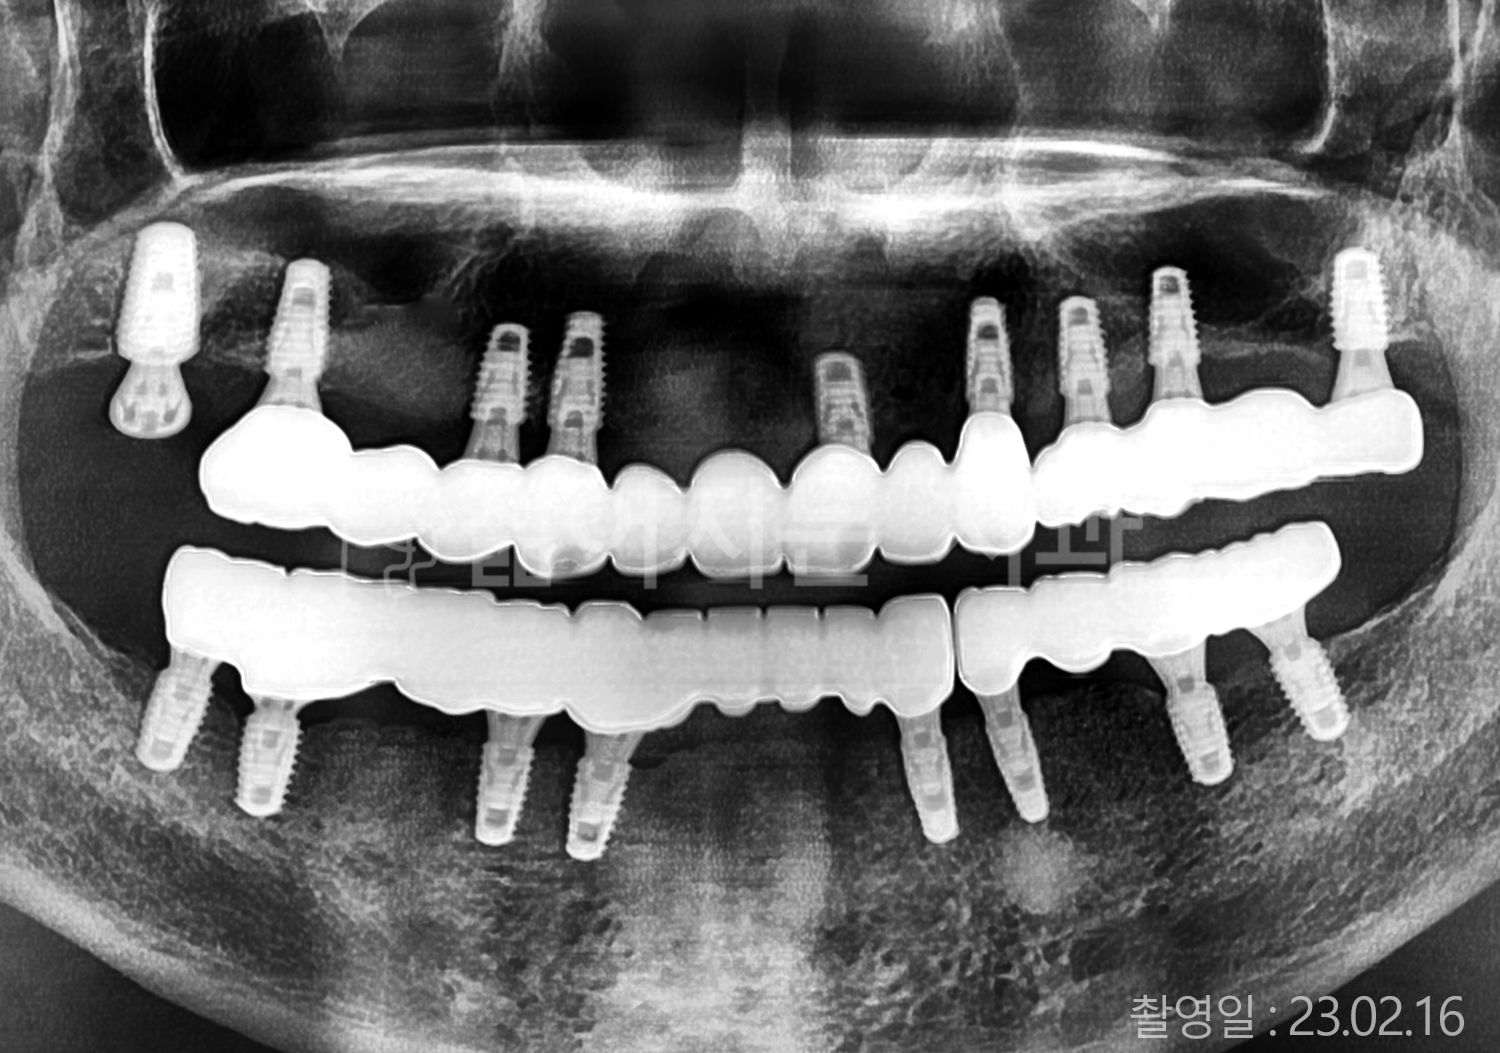

치료부위

식립개수

특이사항